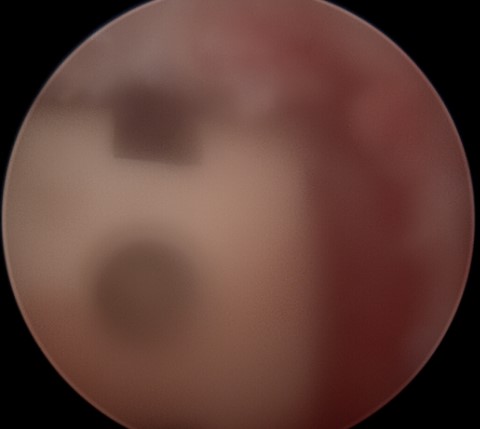

내시경으로 감압과 동시에

추간공을 확공하니

신경통로에 대한 확보 및